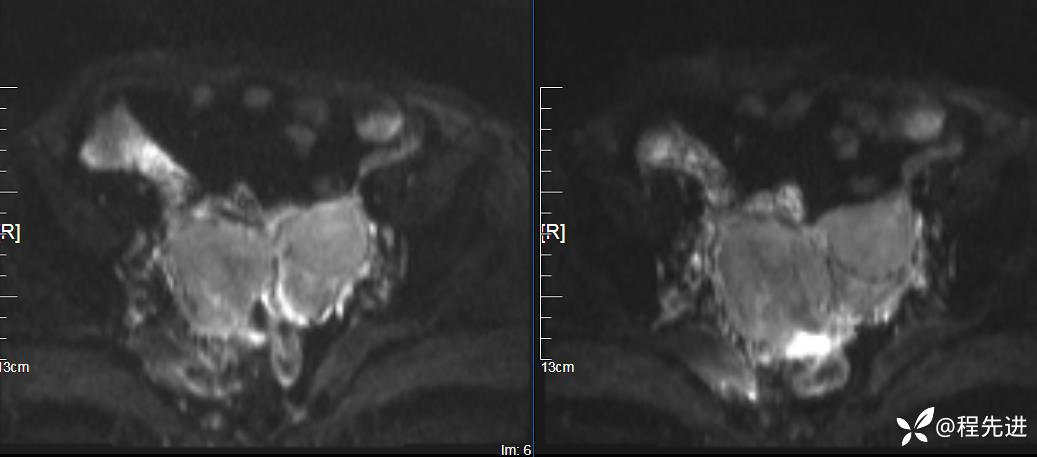

DWI、ADC: